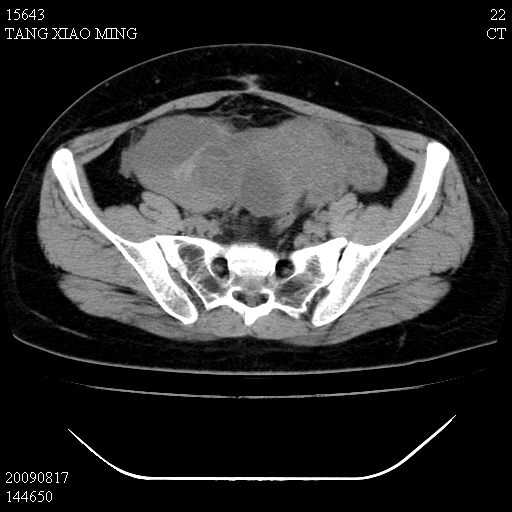

标题: CT21692:盆腔病变

女,33岁,右下腹痛2年余,既往宫外孕病史,如在我院手术,结果下周公布,

可能的诊断。1子宫内膜异位【子宫腺肌症并右卵巢巧克力囊肿】;2 右卵巢囊腺瘤。子宫肌瘤

1)考虑卵巢巧克力囊肿,不排除卵巢囊腺瘤。2)子宫肌瘤可能。

卵巢囊腺瘤,子宫肌瘤,直肠壁厚,不除外占位.